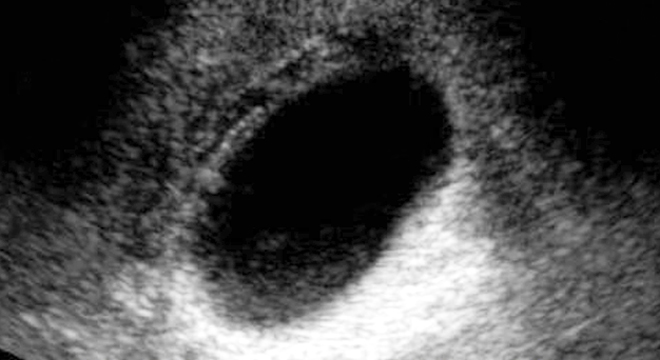

Gallenblasenentzündung im Ultraschallbild

• Ultraschall: Damit lassen sich vorhandene Steine nachweisen